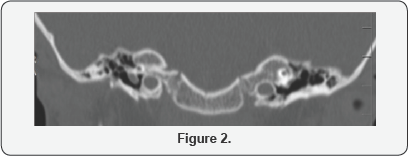

Radiological examination computerized tomography (CT) (Figure 1) scan of temporal bone shows absent cochlea on the right side with large vestibule, with tiny rudimentary cochlea on the left side less than one fluid filled cochlear turn with normal appearing basal turn could not be found, and normal vestibule, lateral and posterior semicircular canals. With high jugular bulb in right side with no bony dehiscence, on both sides the internal acuastic met us was well developed and middle ear structures was normal (Figure 2). Magnetic resonance imaging (MRI) confirmed CT scan finding and also showed normal facial and auditory nerve bilaterally.